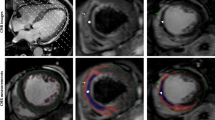

There was no significant difference in the procedure time, radiation exposure time, or contrast volume between the two groups. The number of bleeding events and clinical end points were also not significantly different between the two groups (Table 2). The result of the subgroup analysis (Fig. 2) showed that male patients (RR = 1.46; 95% confidence interval [CI] = 1.09–1.94), non-thrombectomy (RR = 1.40; 95% CI = 1.05–1.86), high thrombus burden (RR = 1.52; 95% CI = 1.07–2.16), door-to-balloon time < 90 min (RR = 1.81; 95% CI = 1.24–2.64), and non-anterior wall infarction (RR = 2.53; 95% CI = 1.60–4.02) had a lower risk for no-reflow phenomenon, which favors PBSG (P for interaction = 0.07). According to the CMR subset, the PBSG can reduce the incidence of MVO and improve cardiac function (Table 3, Fig. 3).

Cardiac magnetic resonance image. The top row was from a patient who under prolonged balloon inflation during stent deployment strategy, there is no imaging features of microvascular obstruction (MVO). Bottom row was from a patient with anteroseptal infarct who under conventional deployment strategy, there is imaging features of MVO (asterisk *)

The indices of angiography for evaluating coronary microvascular circulation in the cardiac catheterization laboratory are semiquantitative and can be subjective. CMR is the gold standard when assessing the MVO, MI size, LV volume, and LVEF, but it is expensive and not yet widely available. The areas of no-reflow have been associated with MVO, as seen on magnetic resonance images, and correlate with a higher degree of myocardial damage. Therefore, in the present study, we designed a subset of CMR to assess the no-reflow phenomenon after PPCI. Approximately 50% of the patients included in this study underwent CMR. The incidence of MVO was 50% in the CDSG and was consistent with previous studies [49]. The prolonged balloon inflation strategy could reduce the incidence of MVO and improve cardiac function, but not infarction size, as evaluated by CMR. The no-reflow phenomenon is associated with poor healing of the infarct scar, including thinner scars and more infarct expansion; therefore, it appears that some therapies can reduce no-reflow without reducing infarct size [50].